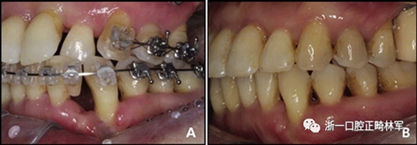

圖13.下頜左側(cè)尖牙近中缺損的改變:A,治療中;B,治療后

治療后頭影測量分析顯示上頜切牙的傾斜和唇部相對于E線的位置都得到改善(表II)。治療前后頭影測量圖的疊加顯示上頜和下頜切牙的向后移動伴隨著上頜切牙的推入。垂直維度在跨學(xué)科正畸綜合治療后被保持。三維模型的疊加顯示了上頜牙列的遠中移動,下頜前牙的回縮和上頜右側(cè)尖牙的推入(圖14)。

圖15.上頜右側(cè)尖牙放射性骨水平:A,治療前;B,治療后

正畸牙齒移動到骨內(nèi)缺損區(qū)域已被報道可以改建缺損區(qū)域的形態(tài),減少其探測深度,并解決骨缺損問題。此外,在正畸運動后牙周缺損區(qū)域出現(xiàn)增強的骨愈合。我們的患者,在正畸治療前3個月進行了全口潔治和下頜前牙區(qū)的刮治術(shù)。拔除預(yù)后不良的下頜左側(cè)側(cè)切牙,該區(qū)域存在嚴重的骨質(zhì)喪失。下頜左側(cè)中切牙和尖牙向缺損區(qū)移動,牙槽骨隨牙齒而移動,側(cè)切牙周圍的缺損得以恢復(fù)。下頜左側(cè)尖牙有一個骨內(nèi)缺損,但缺損的形狀和大小逐漸改善,沒有骨質(zhì)喪失(圖13)。通過正畸牙齒移動產(chǎn)生的牙槽骨預(yù)計將保持穩(wěn)定。